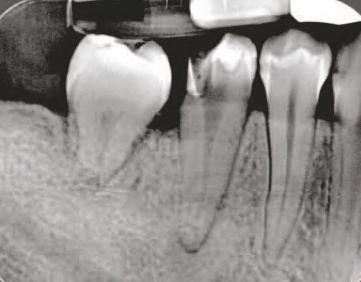

Implantur le pter go d ene au fost def n te ca f nd „[un] mplant plasat pr n tuberoz tatea max lară în placa pter go dă” (f g. 4). Implantur le pter go d ene traversează tuberoz tatea max lară d n reg un le molarulu secund sau terț edentat pentru a se ancora în osul cort cal dens format de peretele poster or al tuberoz tăț max lare, procesul or zontal al osulu palat n ș procesul pter go d al osulu sfeno d.

Aceste mplantur au, de ob ce , un d ametru între 3,5 mm ș 4,3 mm ș o lung me cupr nsă între 18 mm ș 25 mm, cu angulaț ale bontur lor mult -un t de până la 60 grade. Astfel de lung m sunt necesare pentru a as gura că vârful mplantulu se ancorează în osul cort cal al sutur pter gopalat ne după ce traversează țesutul gros adesea prezent în tuberoz tatea max lară. Angulaț a dep nde ș de ungh ul peretelu poster or al s nusulu max lar ș de prox m tatea acestu a față de peretele poster or al tuberoz tăț maxlare. Implantur le pter go d ene au adesea vârfur agres ve în formă de V, ascuț te ș auto-f letante pentru a as gura o ancorare stab lă la mplan-

tare ș colete cu f lete larg pentru a compr ma osul de dens tate scăzută d n reg unea tuberoz tăț max lare.